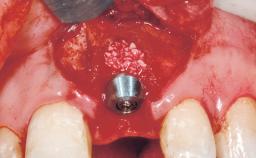

This 43-year-old male patient, a non-smoker, came to our practice because of a fracture of tooth 12 caused by a bicycle accident. Due to the combined para- and infrabony crown and root fracture, tooth extraction, and subsequent implant placement were suggested to the patient as the therapy of choice. The patient had high esthetic expectations with regard to the treatment outcome and asked for an immediate fixed provisional restoration. His individual esthetic risk profile summed up to a medium esthetic risk.

| Placement Protocol | Immediate implant placement |

| Loading Protocol | Immediate |